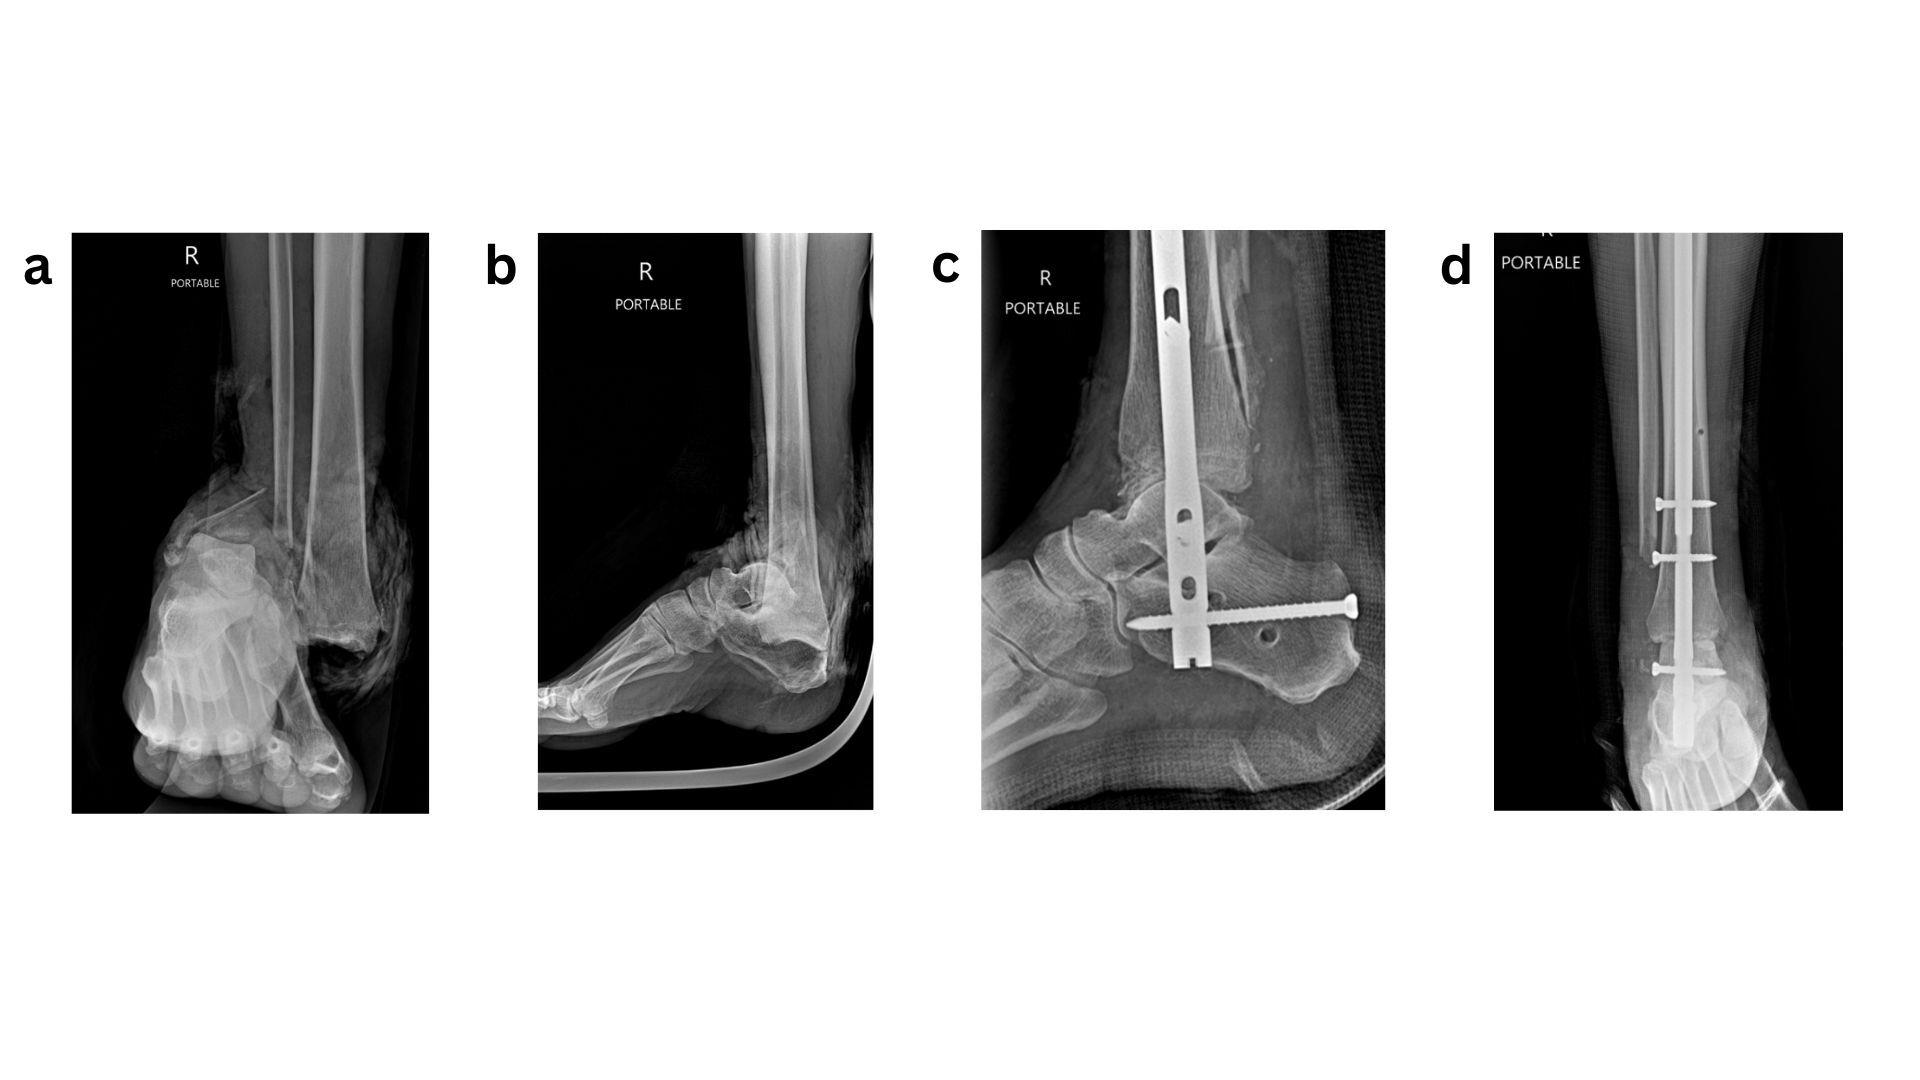

Given that the most severe complications following ORIF of diabetic ankle fractures include the development of Charcot neuroarthropathy or progression to amputation, it is logical to apply principles commonly used in Charcot reconstruction and limb salvage to this patient population. Accordingly, a “modified super construct” or “ORIF plus” strategy has been adopted for the fixation and management of diabetic ankle fractures. Sammarco et al. originally described the super construct concept in Midfoot Charcot surgery as fixation that extends beyond the zone of injury, incorporates bone resection to facilitate deformity correction and reduce soft-tissue tension, employs the strongest fixation tolerated by the soft-tissue envelope, and is applied to optimise mechanical stability.37 These principles should be adapted to diabetic ankle fractures by extending fixation beyond the immediate fracture zone, carefully planning incisions to allow fixation in areas with lower risk of wound complications, utilising the most robust fixation constructs available, and applying them in a mechanically advantageous manner, such as antiglide plating.38 The introduction of locking plate technology has significantly improved fixation in this setting by providing enhanced mechanical stability while preserving periosteal blood supply, which is critical for fracture healing, often without increasing implant bulk. In addition, the use of multiple tricortical/ quadricortical syndesmotic screws has been advocated. In neuropathic ankle fractures, it is routine practice to place three to four syndesmotic screws irrespective of initial evidence of syndesmotic injury, with the aim of maximising construct stability (Fig 1)39. Ankle fracture fixation using standard ORIF techniques is prone to failure when fundamental fixation principles are not rigorously followed. In such cases, limb salvage is best achieved through application of the superconstruct principle, with hindfoot arthrodesis (Fig 2).